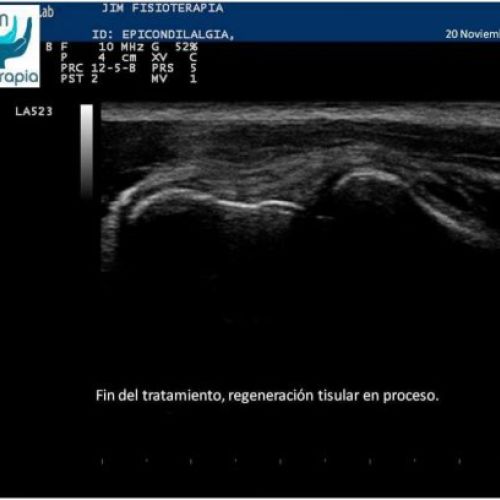

Tratamiento de epicondilitis con EPI®

EPI® Fisioterapia en Madrid para el tratamiento de la epicondilitis